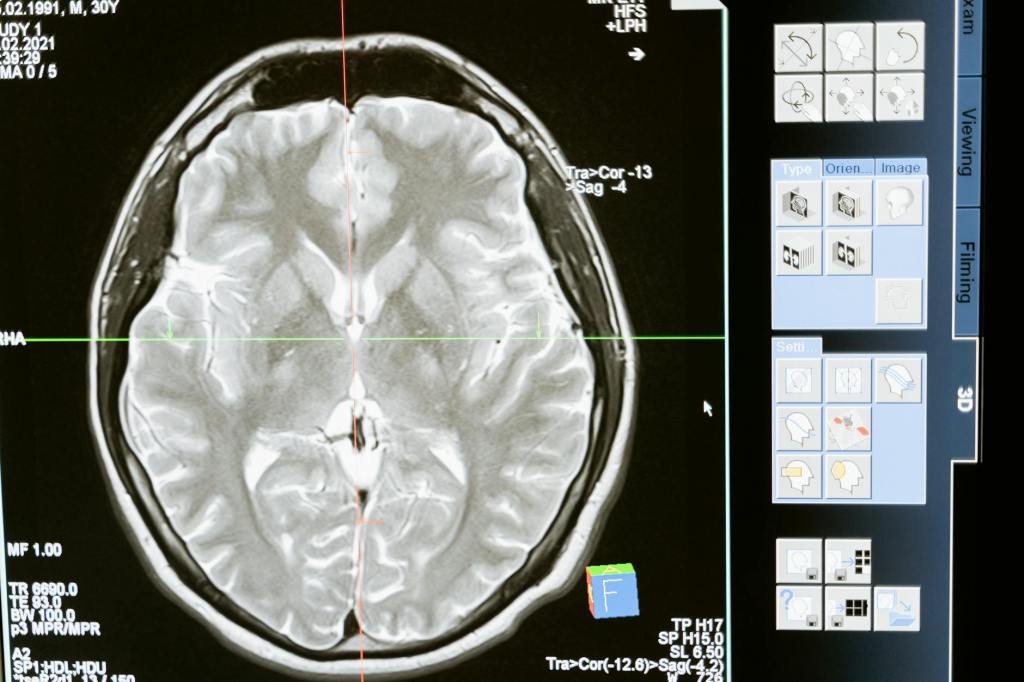

Nell’era della tecnologia avanzata, l’intelligenza artificiale (AI) emerge come un alleato fondamentale nel campo della medicina. Con capacità che vanno dall’analisi di grandi volumi di dati alla personalizzazione dei trattamenti, l’AI promette di rivoluzionare il modo in cui curiamo le malattie e prendiamo cura della nostra salute. Diagnosi Precoce e Personalizzata Uno dei principali vantaggi…